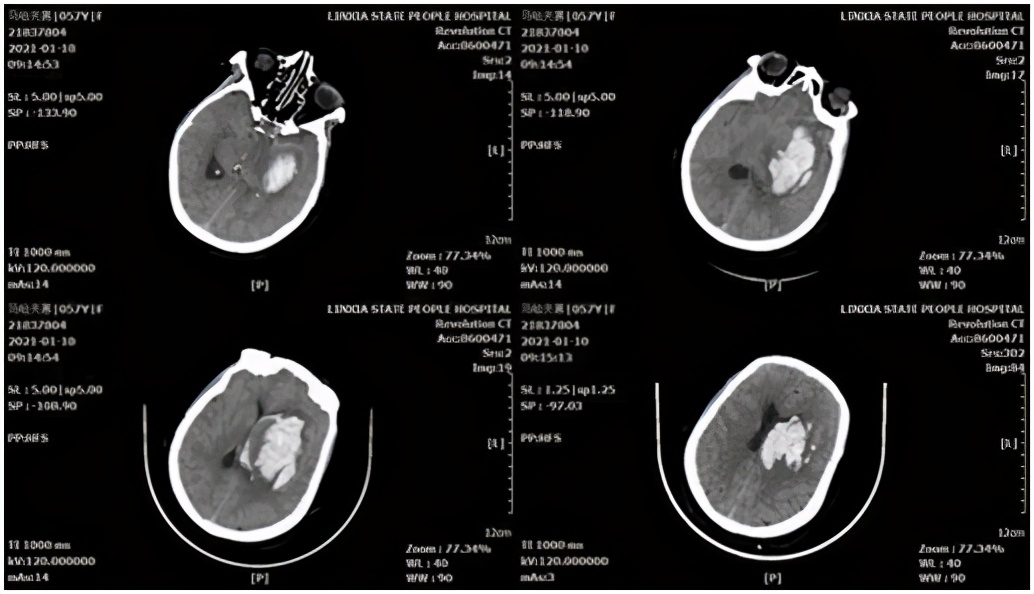

基底节区脑血肿病例,患者女性,58岁。主因“突发意识障碍、呕吐伴右侧肢体无力4小时”,急诊以“高血压脑出血”收入院,头颅CT示显示:左侧基底节区脑出血破入脑室。

术前头颅CT